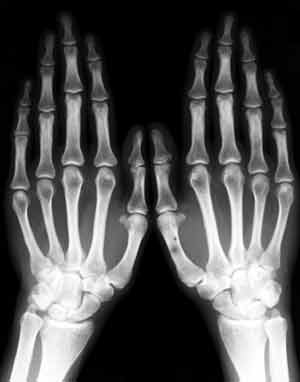

Синдром Марфана.

Рис. 1. Арахнодактилия - удлиненные фаланги пальцев.